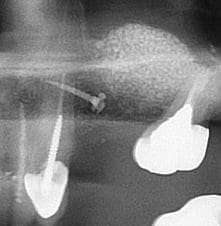

la pano c'est post op ?

Oui c'est bien la pano post op

Image r6habu - Eugenol

Tu es sur que le méat est ouvert de ce coté? on voit pas sur tes images;